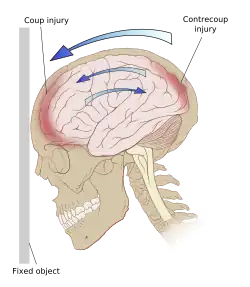

Damage may occur directly under the site of impact, or it may occur on the side opposite the impact (coup and contrecoup injury, respectively).[65] When a moving object impacts the stationary head, coup injuries are typical,[69] while contrecoup injuries are usually produced when the moving head strikes a stationary object.[70]